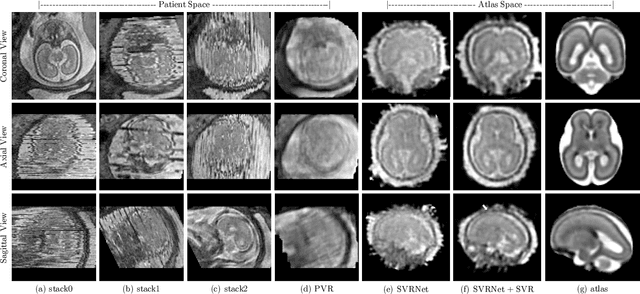

Abstract:In this paper we present a novel method for the correction of motion artifacts that are present in fetal Magnetic Resonance Imaging (MRI) scans of the whole uterus. Contrary to current slice-to-volume registration (SVR) methods, requiring an inflexible anatomical enclosure of a single investigated organ, the proposed patch-to-volume reconstruction (PVR) approach is able to reconstruct a large field of view of non-rigidly deforming structures. It relaxes rigid motion assumptions by introducing a specific amount of redundant information that is exploited with parallelized patch-wise optimization, super-resolution, and automatic outlier rejection. We further describe and provide an efficient parallel implementation of PVR allowing its execution within reasonable time on commercially available graphics processing units (GPU), enabling its use in the clinical practice. We evaluate PVR's computational overhead compared to standard methods and observe improved reconstruction accuracy in presence of affine motion artifacts of approximately 30% compared to conventional SVR in synthetic experiments. Furthermore, we have evaluated our method qualitatively and quantitatively on real fetal MRI data subject to maternal breathing and sudden fetal movements. We evaluate peak-signal-to-noise ratio (PSNR), structural similarity index (SSIM), and cross correlation (CC) with respect to the originally acquired data and provide a method for visual inspection of reconstruction uncertainty. With these experiments we demonstrate successful application of PVR motion compensation to the whole uterus, the human fetus, and the human placenta.